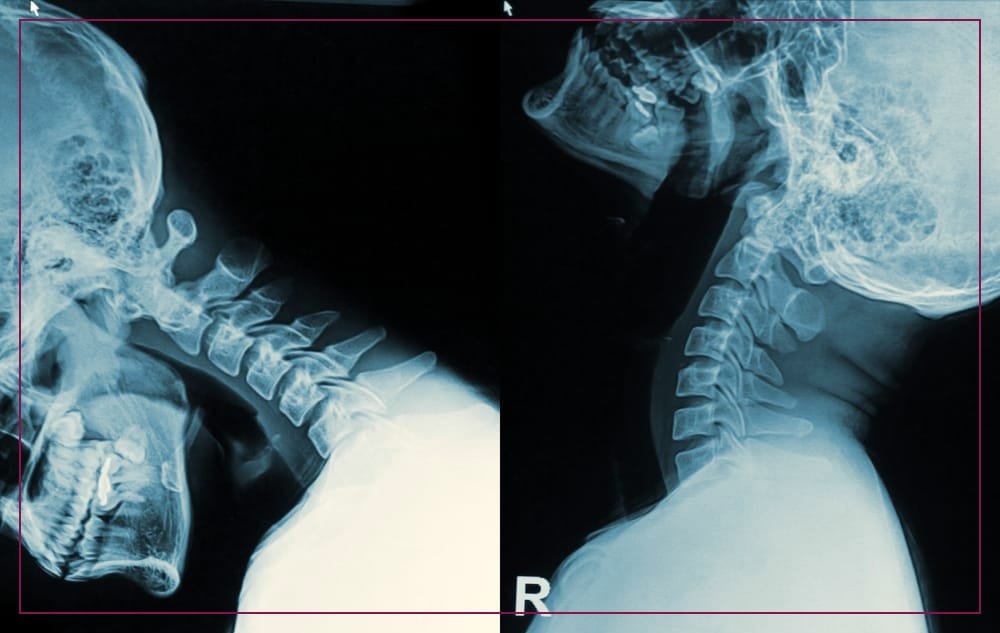

A herniated disc, also known as a slipped or ruptured disc, is a condition that occurs when the soft, gel-like center of a spinal disc protrudes through a tear or weakness in the tough outer layer.

These discs act as cushions between the vertebrae, providing flexibility, and shock absorption, and allowing smooth movement of the spine. When a disc herniates, it can put pressure on nearby nerves, leading to various symptoms such as pain, numbness, or weakness in the affected area.